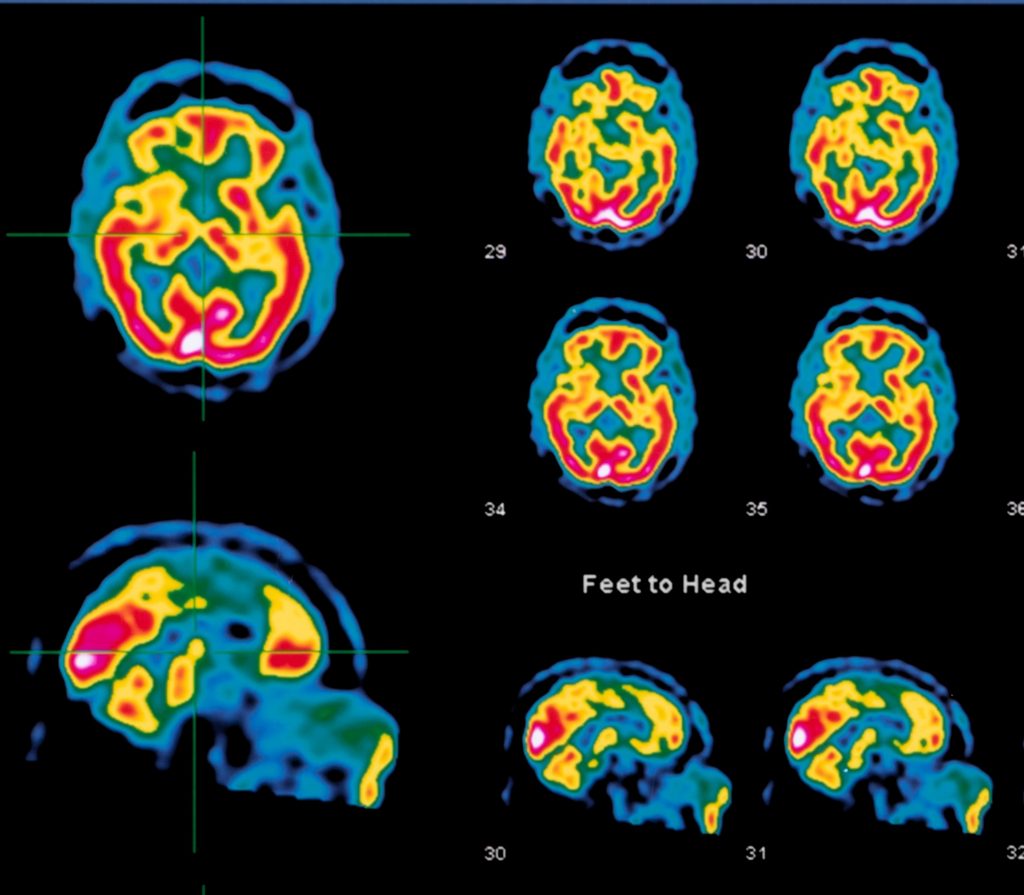

Study: What if mental health is really brain health?

A new brain imaging study based on over 30 years of clinical psychiatric practice shows that mental health should be viewed as brain health. The…